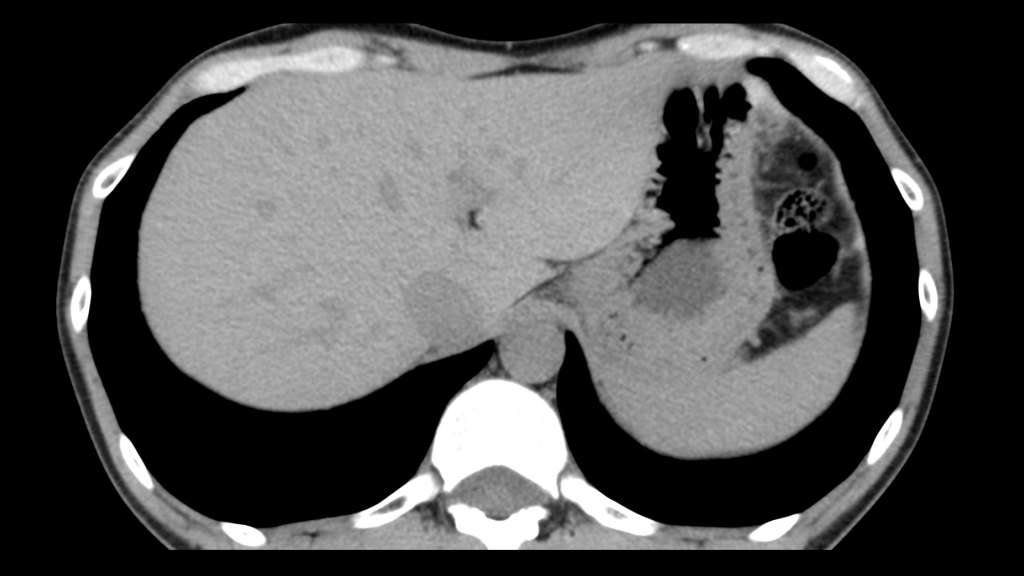

1月18日の単純CT SMV径がSMA径よりも⼩さい 脱⽔や上腸間膜動脈閉塞症 では動脈⾎流が落ち、静脈 が細くなる